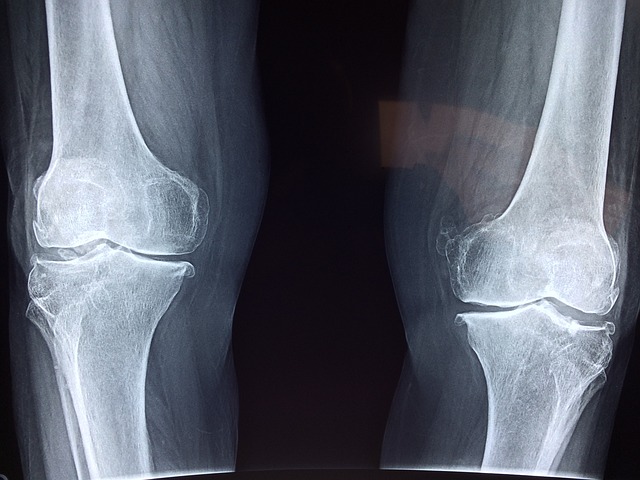

1. 관절염 완화

관절염은 특별한 요인이 없더라도 노화 과정에서 누구나 겪을 수 있는 질병입니다. 보스웰리아 추출물은 관절의 통증과 붓기를 완화시켜주는 등 관절염 개선 효과가 있습니다. 이것은 보스웰리아에 들어있는 소염성분의 효능이라고 합니다.